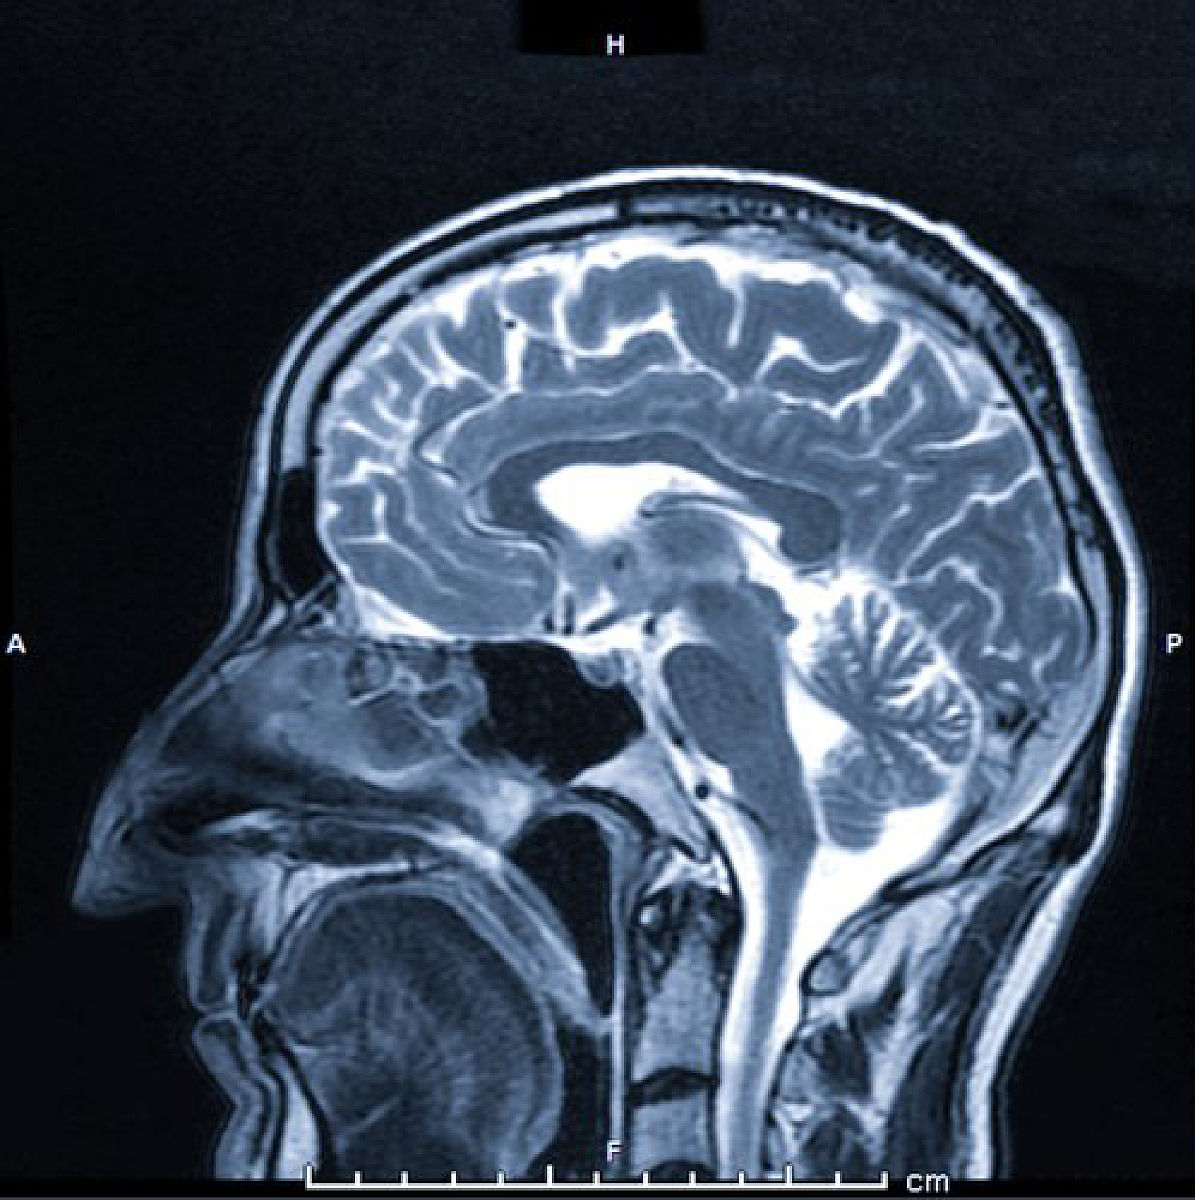

磁共振FLAIR(Fluid-attenuated inversion recovery)是一种磁共振成像技术,它利用了水分子的自由扩散和磁共振信号的相位反转,来抑制脑脊液信号和其他液体信号的影响,从而更好地显示脑组织的病变。具体原理如下:

通过以上两个步骤,磁共振FLAIR成像可以抑制脑脊液和其他液体的信号,从而更好地显示脑组织的病变。在FLAIR图像中,脑脊液和其他液体的信号被抑制,而脑组织的信号则被保留下来,使得脑组织的病变更加清晰可见。